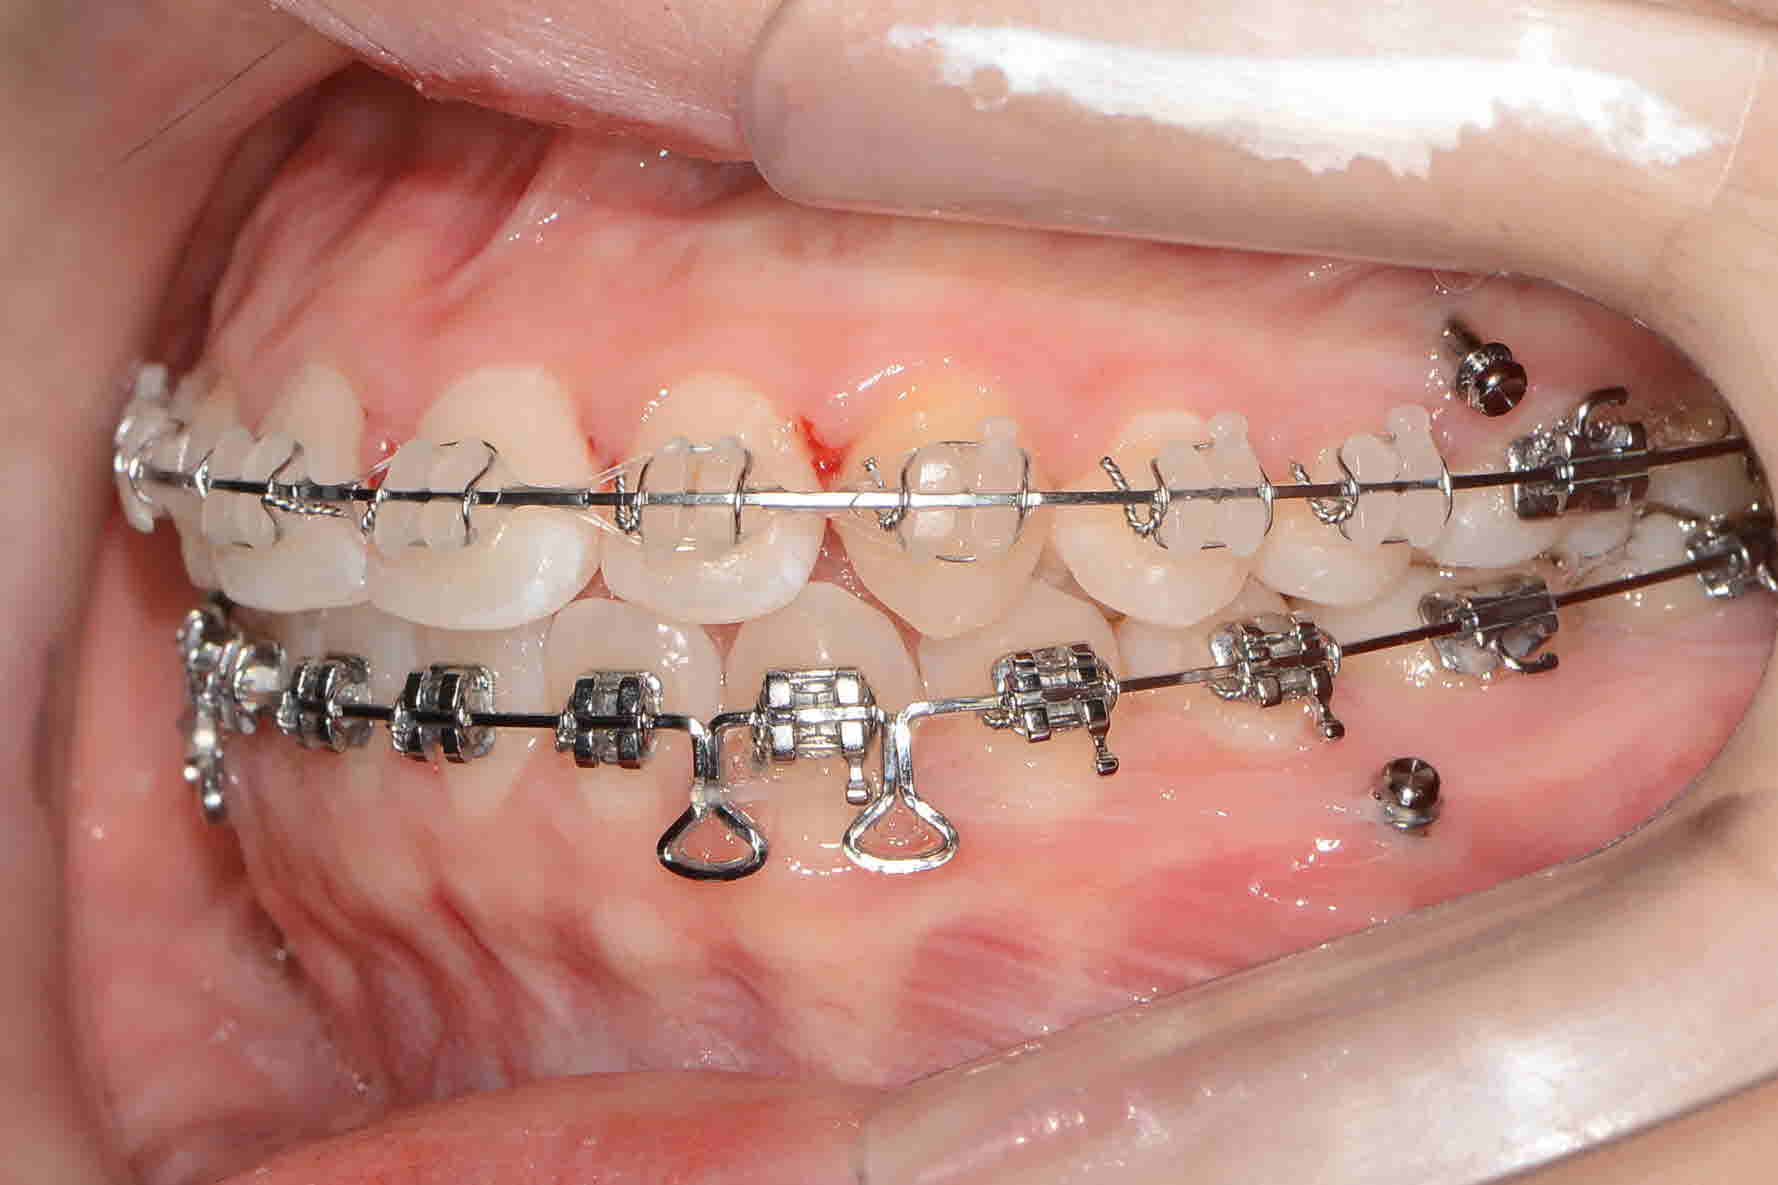

웃을때마다 거슬리는 삐뚤거리는 치아로인해 내원하신 전**님~. 상악은 세라믹 , 웃거나 말을할때 하악보단 상악이 비교적 더 많이보이기때문에 더잘보이는 상악에는 조금더 심미적인 세라믹장치로 하악에는 메탈로 교정치료시작하셨습니다. 앞으로 최선을다해 치료에 힘쓰겠습니다.

교정시작 정면

2017년 6월 정면

2018 년 4월 정면

교정완료 정면